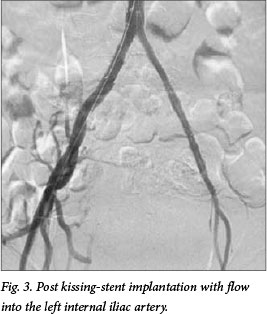

A postprocedural arteriogram revealed adequate flow into the left internal iliac artery. Femoral pulses were palpable after the procedure. Clopidogrel was prescribed for an indefinite period. His postoperative course was unremarkable with complete resolution of his rest pain and an improvement of his ABI to 0.85 on the left. This was unchanged at the 6-month follow-up. He is assessed periodically and remains symptom free 2 years after the index procedure.

In our case, the patient had occlusion of the left common and external iliac arteries. We opted not to place long stents from the aorta into the left common femoral artery. The main body of the internal iliac artery was adequately patent with good collateral-isation to the femoral arteries (Fig. 3). Kissing stents were mandatory owing to the flush-left common iliac occlusion and the right common iliac stenosis. By performing kissing aortoiliac stenting and extending the left stent into the internal iliac artery, we were able to reperfuse the left leg and eliminate the patient's rest pain.